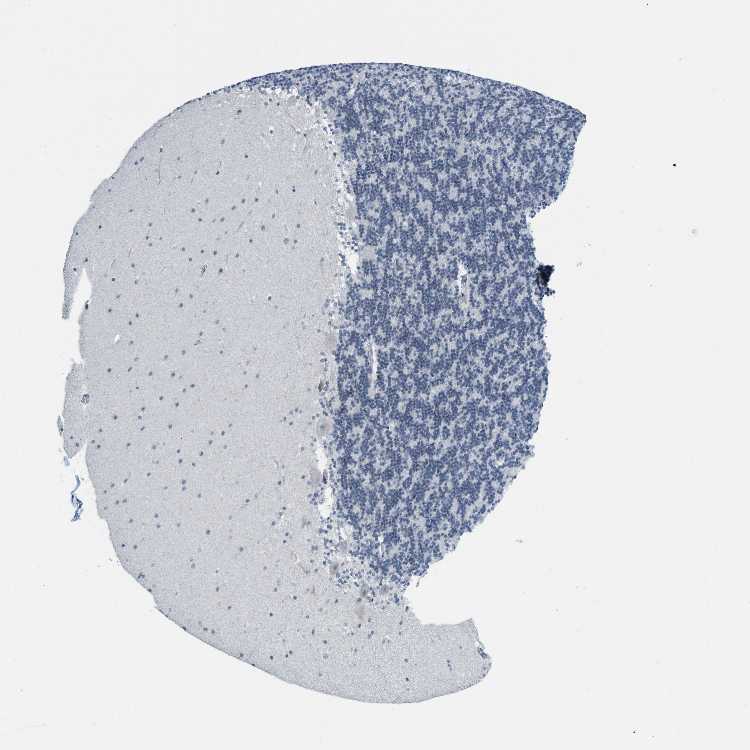

CEREBELLUM - Expression summary

CEREBELLUM - Antibody stainingi

Antibody staining in the annotated cell types in the current human tissue is reported as not detected, low, medium, or high, based on conventional immunohistochemistry profiling in selected tissues. This score is based on the combination of the staining intensity and fraction of stained cells.

Each image is clickable and will lead to virtual microscopy that enables deeper exploration of all samples and also displays staining intensity scores, fraction scores and subcellular localization as well as patient and tissue information for each sample.

Antibody HPA003505Antibody HPA003881Antibody CAB018768

Purkinje cells MediumNot detectedNot detected

Cells in granular layer HighLowNot detected

Cells in molecular layer HighNot detectedNot detected